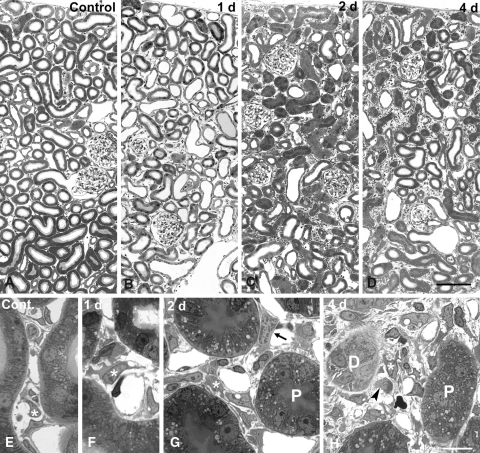

Fig. 1.

Rat renal cortex of contra lateral (a, e) and of ureter ligated (b–d, f–h) kidneys; 1 μm epon sections. Overviews (a–d) show the dilatation of distal segments after 1 day, the collapse and shrinkage of predominantly proximal tubules after 2–4 days and the progressive enlargement of the interstitium. Higher magnifications (d–h) reveal the increasing complexity of interstitial cells; asterisk fibroblasts; D distal segment, P proximal tubule (cut tangentially in H); arrow fibroblast in prophase of mitosis, arrowhead mononuclear cell in mitosis. Bara–d ~100 μm, e–h ~10 μm

Distal segments and collecting ducts

After 1 day dilation of the luminal diameters of most distal segments was eye-catching (Fig. 1b). Occasionally their lumen was filled with hyaline material. From day 2 on cellular hypotrophy associated with a collapsed lumen, as described above for proximal tubules, became apparent also in distal segments. At day 4 many distal profiles were massively shrunken and atrophic (Figs. 1d, h, 3). However, some profiles remained histologically almost normal up to day 4. The diameters of collecting duct profiles were dilated from day 1 on and their largely open lumina were strikingly prominent among the shrunken tubular profiles in the cortex at day 3 and 4 (Fig. 1c, d).